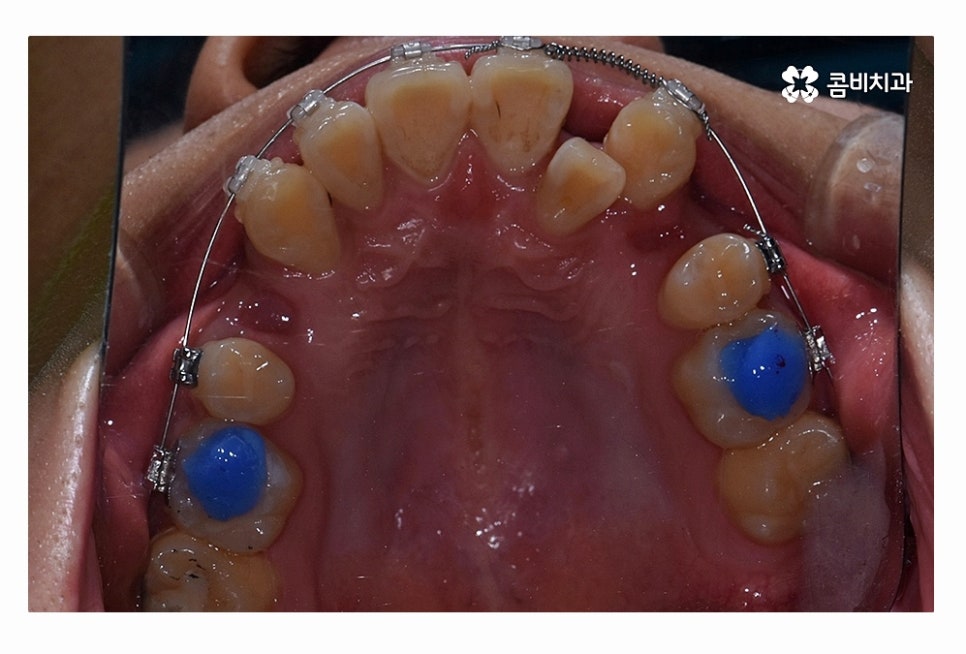

오늘 보시는 환자분의 사례처럼 덧니가 치아끼리 겹쳐 있는 경우에

치아의 이동 공간 확보를 위해서 덧니 발치 필요한 사례였으며

교합과 치아교정 후 얼굴 변화를 고려할 때도 치아교정 과정에서

발치가 필요한 사례였다고 볼 수 있어요.